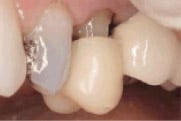

Figure 1

Initial situation:

Decay, fractured buccal cusp and unsupported lingual cusp on tooth

No. 20, buccal view.